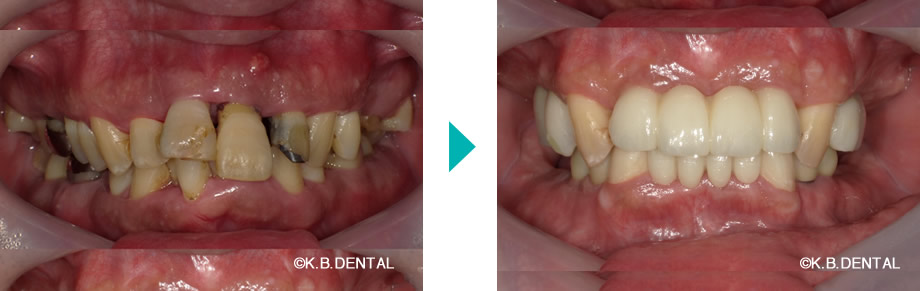

嘔吐反射改善の症例

パノラマ:嘔吐反射症例

口元:嘔吐反射症例

口腔内:嘔吐反射症例

極度の嘔吐反射で、咬合が崩壊した状態からインプラントで回復させた症例です。

嘔吐反射が著しく、奥まで歯ブラシができない場合は、状況により上下共に5番目の歯まで補綴して、ご自身でもメンテナンスしやすいように治療します。

費用:麻酔代込み総額約500万円